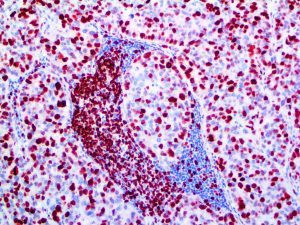

It is the ICU physician who is most likely to witness one of the deadliest manifestations of the abnormal immunological response, the cytokine storm syndrome (CSS). This response is also referred to by some as the cytokine release syndrome (CRS). CSS is characterized by continuous activation and expansion of macrophage and lymphocyte populations, which secrete large amounts of cytokines, causing the cytokine storm. This massive cytokine release is akin to hemophagocytic lymphohistiocytosis (HLH) disease, a syndrome characterized by initial unchecked and persistent activation of cytotoxic T lymphocytes and NK cells.

Clinical and laboratory manifestations of HLH include fever, enlarged liver and/or spleen, neurologic dysfunction, coagulopathy, liver dysfunction, cytopenias (i.e., low levels of erythrocytes, leukocytes, and/or platelets), hypertriglyceridemia, hyperferritinemia, hemophagocytosis, and eventually diminished NK cell activity as the immune system becomes progressively paralyzed. HLH can be familial (primary HLH) or secondary to another disease process (sHLH), such as rheumatic disease, in which it is referred to as macrophage activation syndrome (MAS, characterized by elevated ferritin).